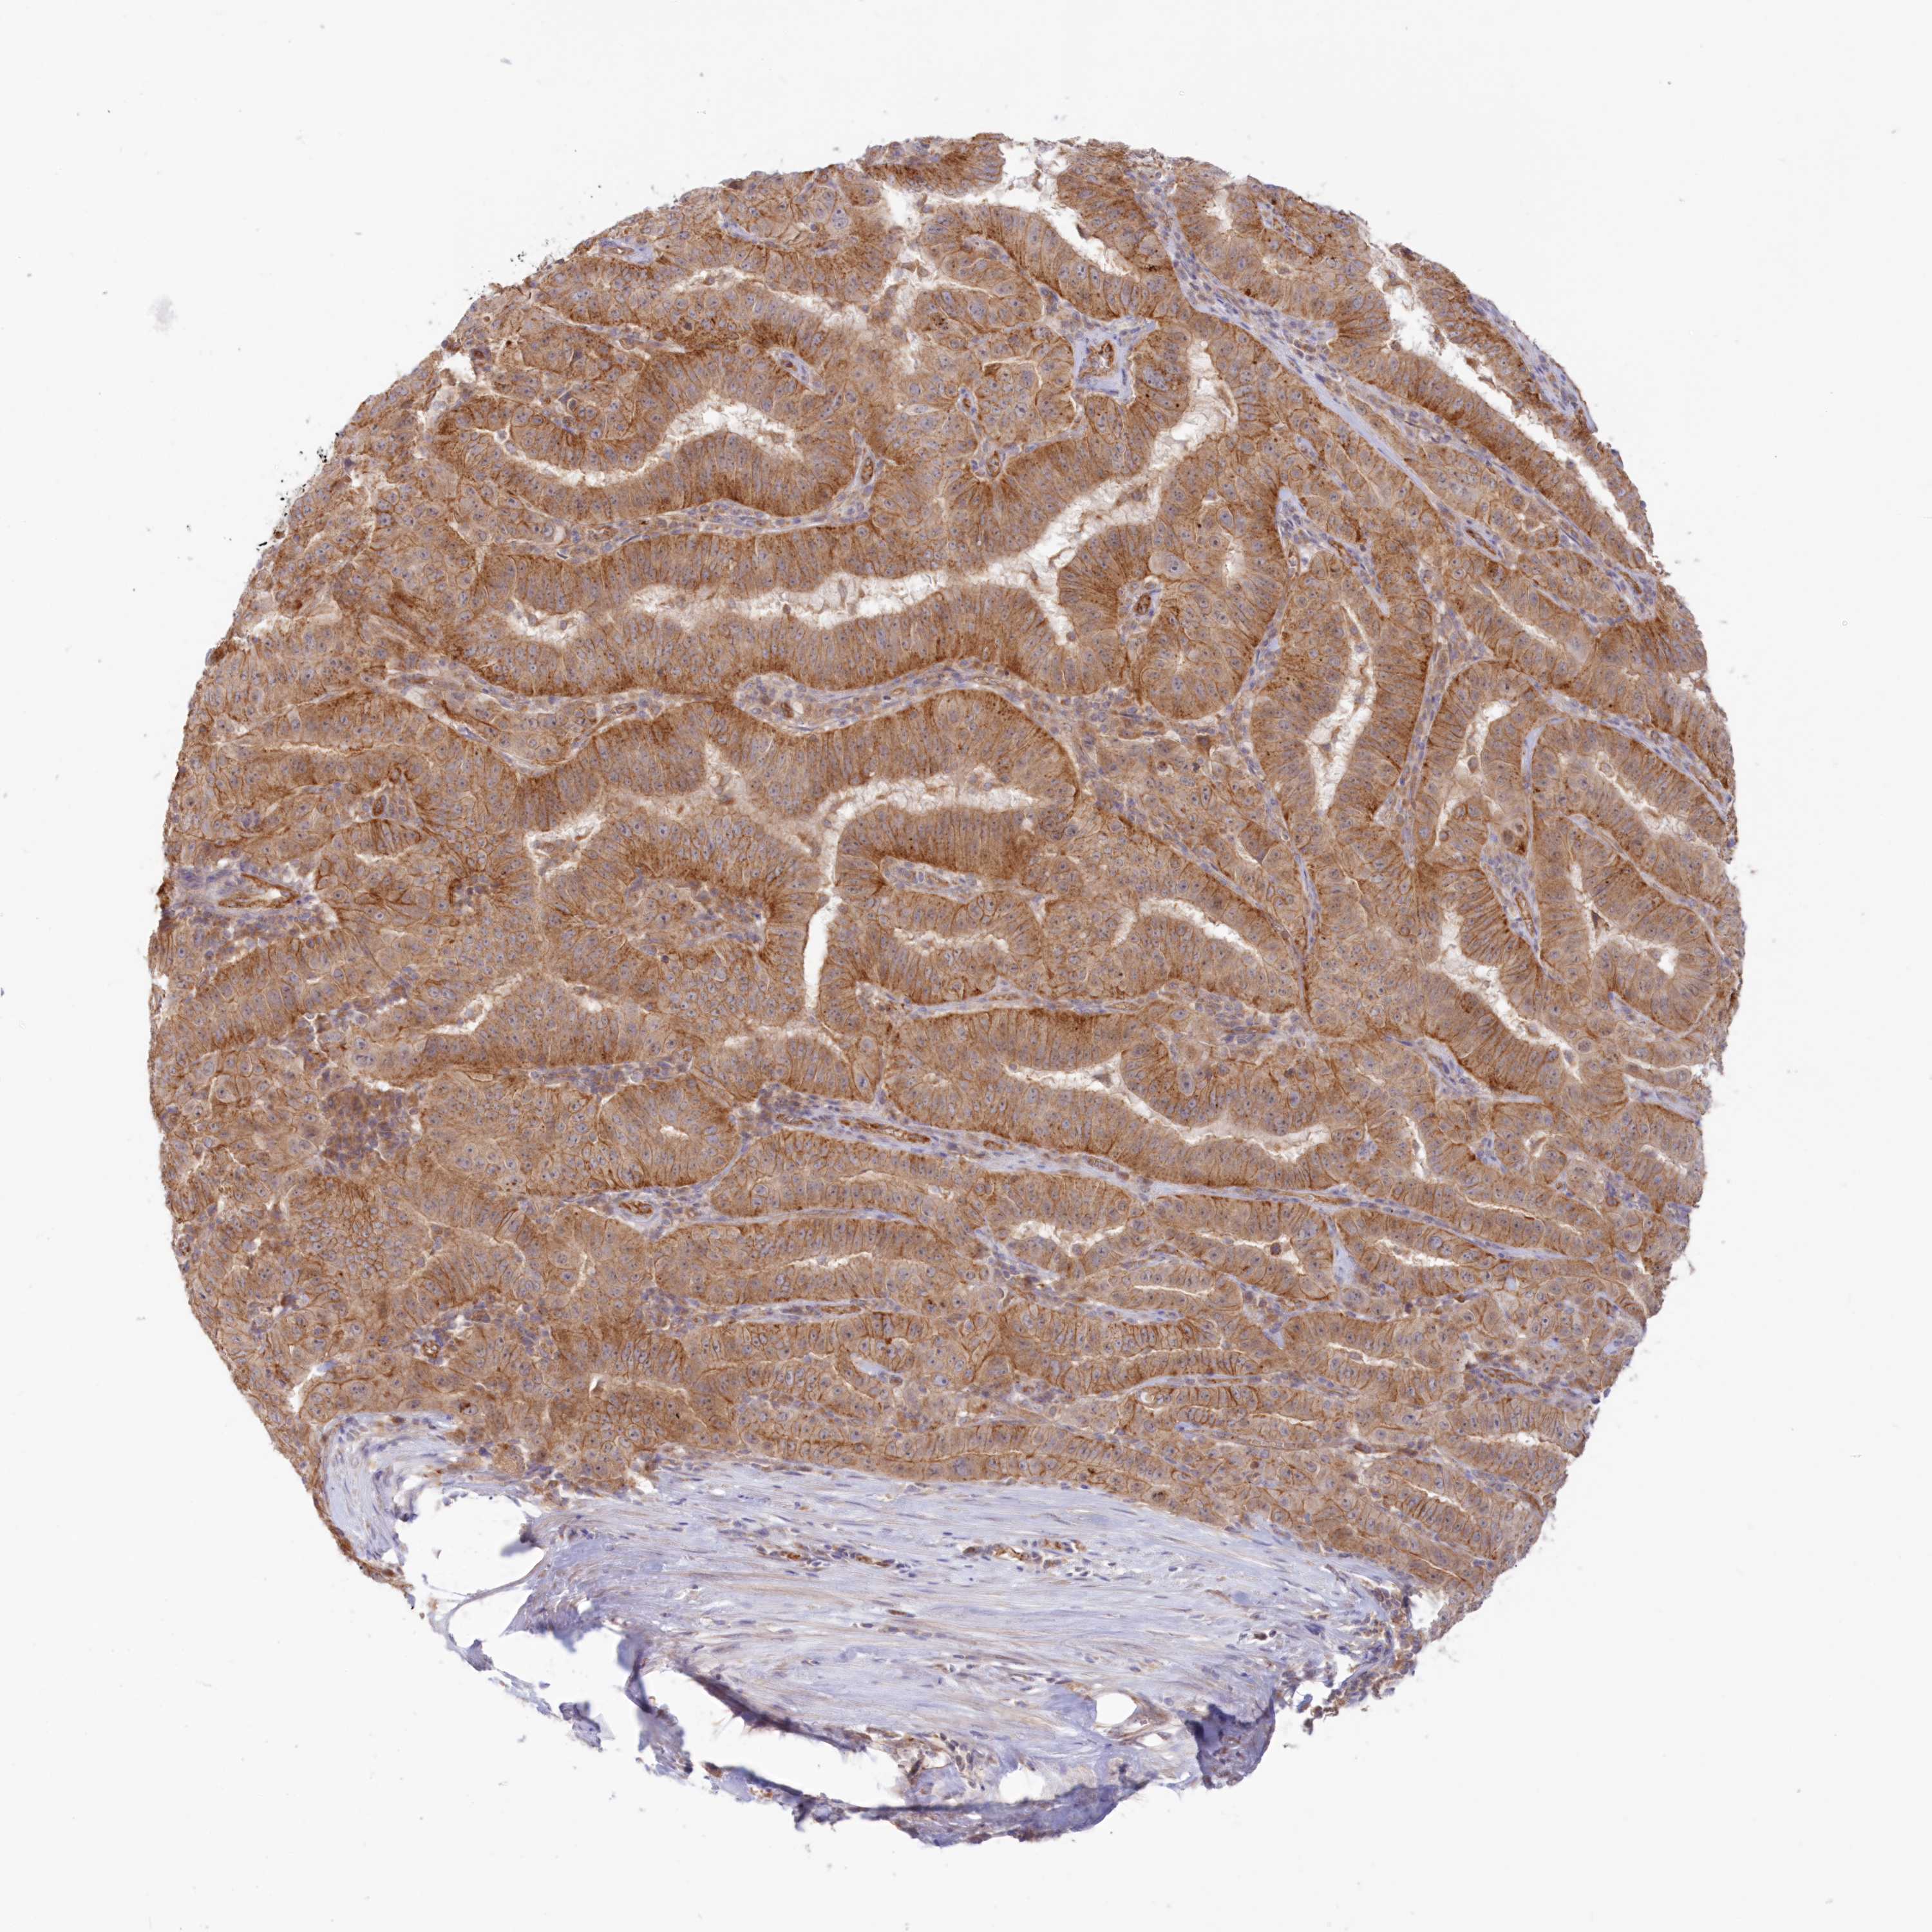

PANCREATIC CANCER - Protein expressioni

A mouse-over function shows sample information and annotation data. Click on an image to view it in a full screen mode. Samples can be filtered based on level of antibody staining by selecting one or several of the following categories: high, medium, low and not detected. The assay and annotation is described here.

Note that samples used for immunohistochemistry by the Human Protein Atlas do not correspond to samples in the TCGA dataset.

Antibody stainingi

Antibody staining in the annotated cell types in the current human tissue is reported as not detected, low, medium, or high, based on conventional immunohistochemistry profiling in selected tissues. This score is based on the combination of the staining intensity and fraction of stained cells.

Each image is clickable and will lead to virtual microscopy that enables deeper exploration of all samples and also displays staining intensity scores, fraction scores and subcellular localization as well as patient and tissue information for each sample.

Antibody HPA030943

Antibody HPA030944

Antibody HPA030945

Antibody CAB034184

Staining

High

Medium

Low

Not detected

Intensity

Strong

Moderate

Weak

Negative

Quantity

>75%

75%-25%

<25%

None

Location

Nuclear

Cytoplasmic/membranous

Cytoplasmic/membranous,nuclear

Adenocarcinoma, NOS